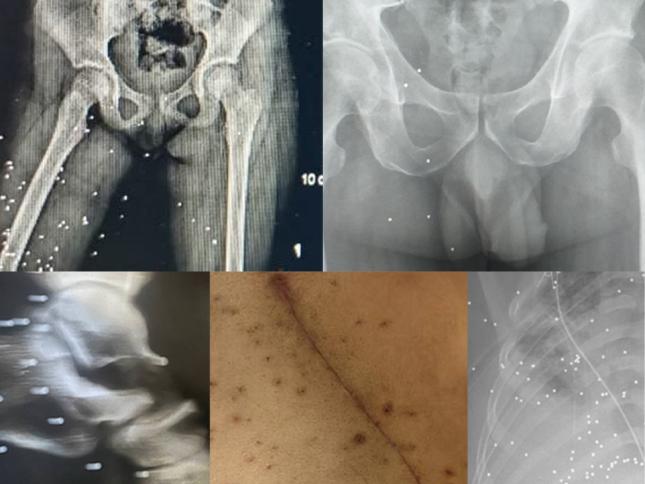

سیاسی و اجتماعی تصاویر و روایتهای تکاندهنده از شلیک به اندام جنسی معترضان پس از شلیک، یکی از ماموران او را لمس کرد و هدف آزار جنسی قرار داد: «همزمان با خونریزی، تحقیر و توهین میکردند. نمیخواستند متفرقمان کنند، بلکه میخواستند ما را خرد کنند» «خسته شو دیگه، تا کی تیر جنگی؟»؛ گلولههایی که مستقیم به سر و گردن میخوردند «گلوله در تن، هراس از درمان»؛ هزاران مجروح به دلیل حضور ماموران به بیمارستان نرفتهاند بازداشت برادر برای تسلیم او؛ روایت فریب و قتل عباس رشیدی در سمیرم اصفهان